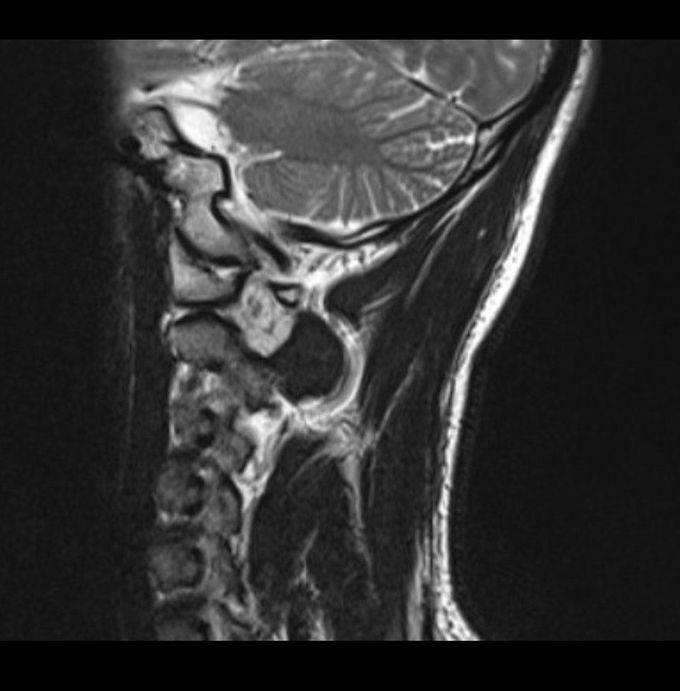

Unknown cervical mass

Does anyone know what this image shows? 41yo male patient with years of neckpain.